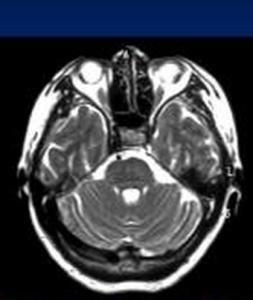

(2)磁共振成像檢查可見面神經,尤其是膝狀神經節部位長T信號。